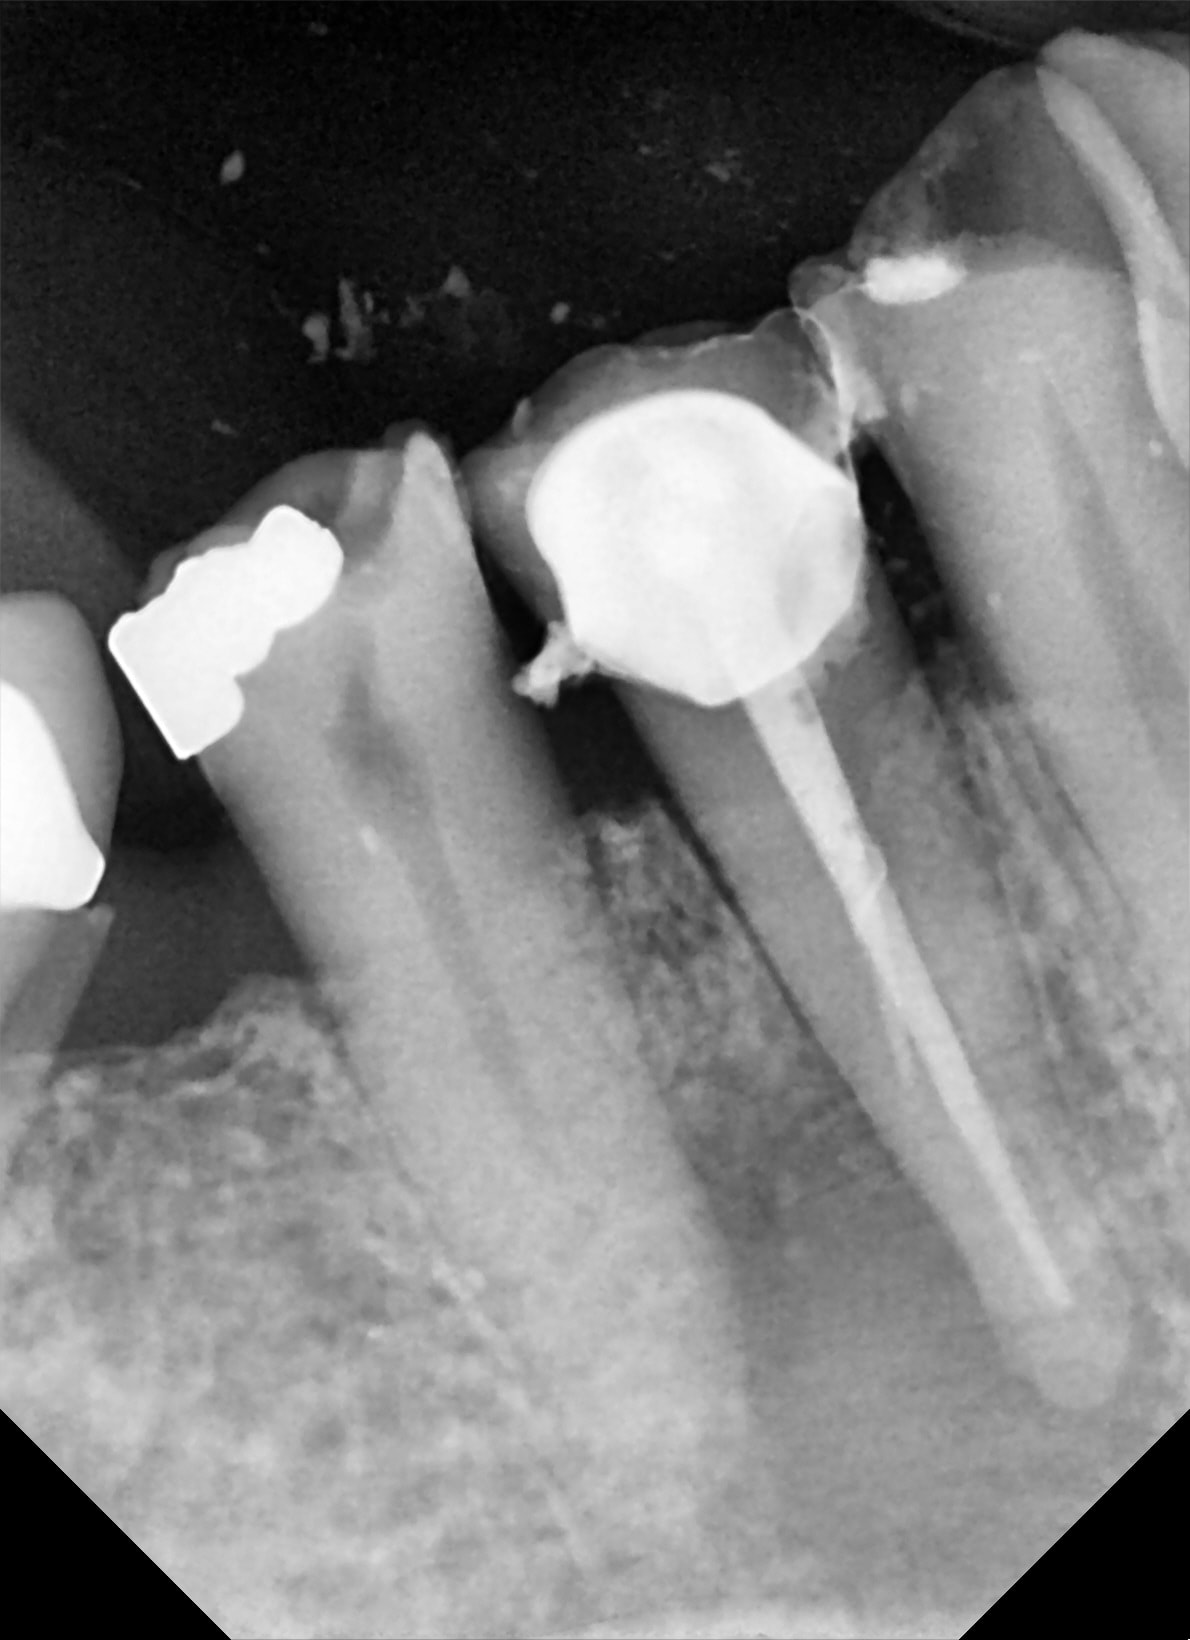

Je lui ai fait 2 devis IC à déposer et retraitement.... vue sa tronche devant le devis je sens que ça ne va pas le faire.

Je vais lui faire une ERI gracieusement si il ne peut pas financièrement :)

RDV dans un mois .....

ayé c'est fait !

sous pradaxa ( ou l'autre je sais plus), ça a coulé à flot.

Du coup j'ai coller au superbond.

2 nhulan - Eugenol

1 jaojme - Eugenol